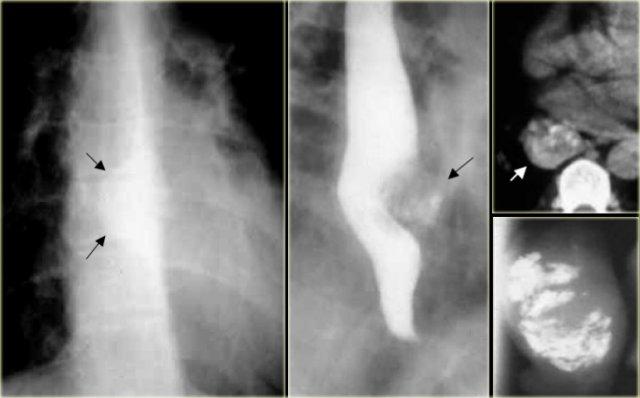

Hình ảnh ngoài cùng bên trái cho thấy vị trí hẹp (mũi tên) với các nếp niêm mạc không đều tại vùng hẹp trên hình ảnh đối quang không khí.

Bệnh nhân này được chẩn đoán thực quản Barrett.

Hẹp và loét thực quản đoạn giữa cần nghi ngờ thực quản Barrett.

Hai hình ảnh bên phải cho thấy thực quản Barrett với vùng hẹp không đều do ung thư biểu mô tuyến.

Hình ảnh cho thấy đoạn hẹp lành tính dài, thon đều đối xứng xuất hiện nhiều tháng sau xạ trị.

Hình ảnh của bệnh nhân có đoạn hẹp lành tính ở vị trí cao của thực quản (mũi tên).

Có hình ảnh đông đặc phổi thùy dưới hai bên do hít sặc tái diễn nhiều lần.

Hình bên trái cho thấy đoạn hẹp ở vị trí cao (mũi tên) sau khi nuốt phải chất ăn mòn.

Gai xương (mũi tên) có thể chèn ép vào thực quản và hạ họng.